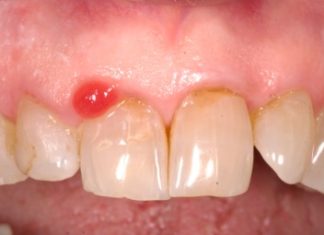

Mantenimento del profilo tissutale nell’impianto post-estrattivo ritardato: obiettivo realistico?

Gestione chirurgico-protesica di un sito implantare post-estrattivo, con focus sulla gestione del profilo tissutale nell’impianto post-estrattivo mediante il restauro provvisorio, utilizzato come supporto per...